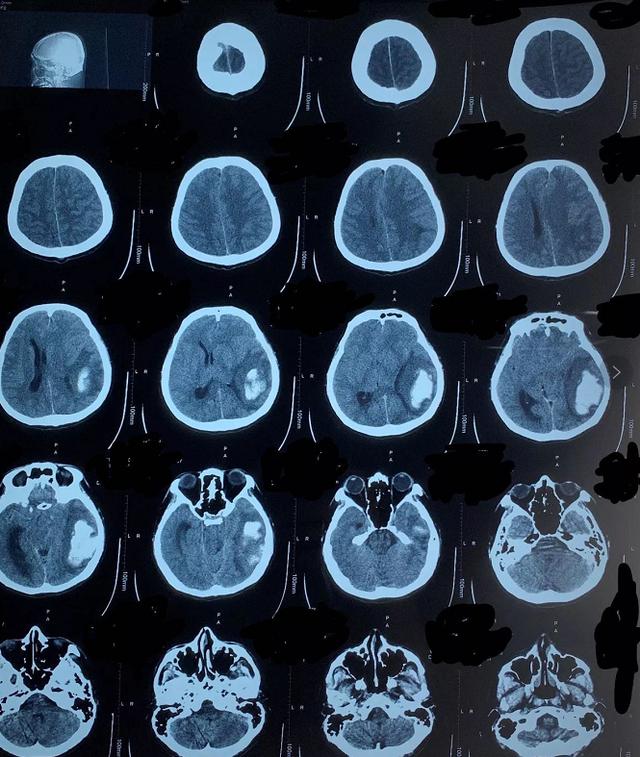

头颅CT提示 , 患者左侧大脑半球大量脑出血 , 脑水肿明显 , 如病情进展随时可能危及生命 。 专家们当机立断 , 安排患者收住神经内科病房 。

几经讨论 , 专家们制定了详细的脱水降颅压方案及对症治疗措施 , 患者入院初期病情曾一度好转 。 然而 , 住院第5天 , 患者病情突然发生进展 , 突发昏睡 , 双侧瞳孔不等大、小便失禁 。 专家们一直担心的事情还是发生了——脑疝 。

随着辅助检查的不断完善 , 病情变得更为复杂 。 患者入院检查疟原虫抗体阳性 , 连续口服抗疟药5天仍间断阵发性肢体抖动 。 专家果断将治疗方法升级为静脉抗疟治疗 。 治疗第3天 , 患者抖动终于消失 , 却又突发高热 , 不能进食 。 检查结果提示 , 患者出现了重症感染 。 医疗队再度调整、升级了治疗方案 , 并持续关注着颅内病变进展情况 。